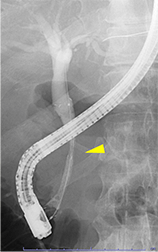

総胆管結石や悪性腫瘍(膵癌、胆道癌)などによって胆道の流れが滞り、黄疸や感染がみられる場合はプラスチックや金属性のステントを胆管に挿入して胆汁の流れをよくします。

膵癌による胆管狭窄

胆管ステント留置後